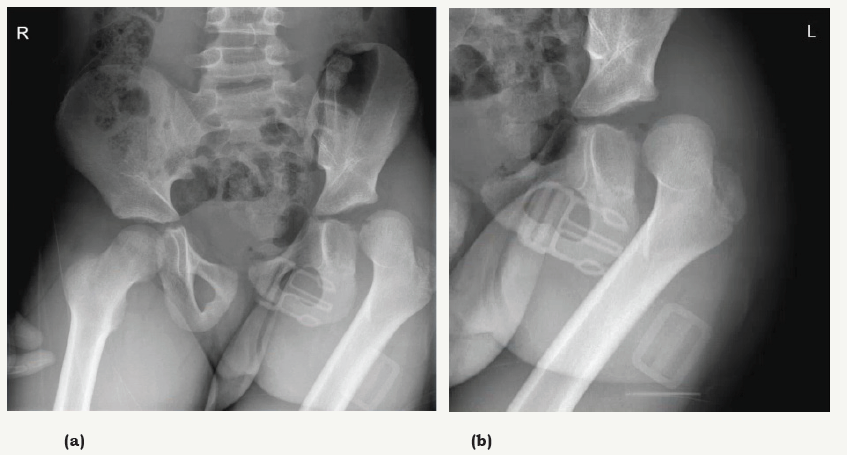

AP X-ray of the pelvis and hip demonstrated a posterior dislocation of the left hip without any associated fractures.

Traumatic dislocations of the hip in children are uncommon. 80% of these are posterior dislocations caused by axial force on a flexed, adducted and internally rotated hip joint [2]. Due to ligament laxity and a soft pliable acetabulum this emergent injury can be caused by low energy traumas such as typical child play or even tripping without associated fractures [3]. In children older than 10 years, high energy (e.g. MVA) is needed to cause this injury and associated fractures are thus more common [4] (Figure 1)

Low energy trauma and a leg in fixed internal rotation, adduction and slight flexion can guide to a correct diagnosis. AP pelvis- and hip radiographs confirm diagnosis and warrant for emergent closed reduction if no associated fractures are present.

Figure 1: AP pelvis- and hip X-ray showing posterior hip dislocation without associated fractures.